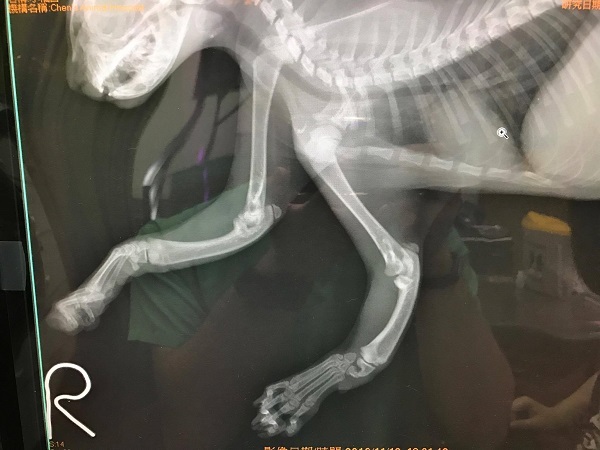

主題: 疑似前肢斷裂受傷小貓 申請者姓名: Funson Lee 花色: 申請日期: 2016-11-26 21:34:42 申請者部落格: 申請者臉書網址: 所在縣市/合作醫院: 桃園縣/陳獸醫院 治療費用: 7740元 需求人數: 17人 已結案 (2022-05-13 15:20:54) 報名人員: 若芝 x2(已付款)、Jill S.(已付款)、Selene Tsai、Iris Hung x2(已付款)、薇薇安(已付款)、王小盈(已付款)、歡喜(已付款)、Fox Yo(已付款)、Ray0322(已付款)、Anq Liao x3(已付款)、May x3(已付款)、SweetTpg(已付款)、 候補人員: 動物病情說明: 我是桃園區域的志工~

經X光片拍照後~發現 小貓先天性橈骨發育不全!

也無法開刀矯正治療~